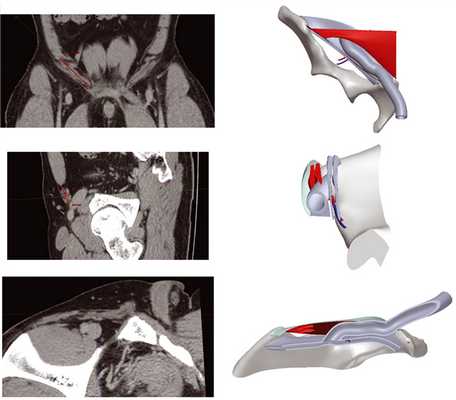

На заключительном этапе работы с данными КТ с применением оригинального алгоритма [12] была выполнена автоматическая сегментация некоторых КТ-исследований в программе Инобитек DICOM-Viewer. Редактирование полученной сетки выполняли в программе MeshLab (рис. 12).

Рис. 12. Трехмерные модели (а—в) передней брюшной стенки и паховой области пациента [12].

Получение подробных трехмерных моделей передней брюшной стенки пациента до начала операции в натуральном масштабе на основе данных КТ- исследования позволяет:

— учесть особенности анатомического строения, деформации и повреждений пахового канала, приводящие к патологическому выпячиванию органов брюшной полости;

— определить форму сетчатого имплантата в соответствии с индивидуальными особенностями анатомического строения брюшной стенки пациента и произвести индивидуальный по размерам и форме имплантат;

— произвести последующую коррекцию формы сетчатого имплантата;

— составить подробный план проведения операции.

На основании данных, полученных при изучении виртуальных срезов, сделанных с помощью ПО Vidar DICOM Viewer, на основе трехмерных реконструкций в ПО SolidWorks была построена трехмерная параметрическая (статистическая) модель пахового канала, включающая следующие структуры: фрагмент таза, паховая связка, поперечная фасция, переходящая во внутреннюю семенную фасцию семенного канатика, нижние эпигастральные сосуды, нижние края левых внутренней косой и поперечных мышц, апоневроз наружной косой мышцы живота. Выбор вышеуказанных структур был сделан с точки зрения практической целесообразности. С помощью созданной модели был рассчитан объем щелевидного промежутка пахового канала для разных типов телосложения и выполнена разработка основных этапов предложенного оперативного вмешательства (рис. 13, 14).

Рис. 13. Сопоставление срезов, выполненных в ПО Vidar DICOM Viewer и созданной параметрической модели пахового канала при различном положении в пространстве.

Рис. 14. Статистическая параметрическая модель пахового канала, построенная на основе топографо-анатомических измерений в ПО Vidar DICOM Viewer.